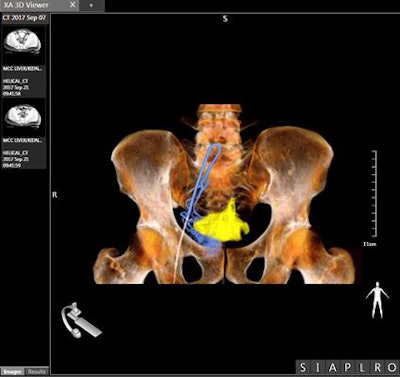

Image of prostate cancer embolization acquired with Canon's Alphenix interventional system in 4DCT mode. Image courtesy of Canon Medical Systems.An interventional suite that pairs an angiography system with a CT scanner -- called Alphenix 4D CT -- also is being demonstrated at the vendor's booth. The suite matches an Alphenix Sky + C-arm with an Aquilion One Genesis volumetric CT scanner, enabling clinicians to plan, verify, and treat patients in a single session.